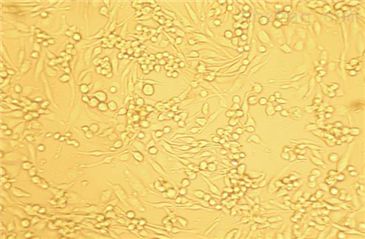

| 2. 仔细阅读细胞说明书,了解细胞相关信息,如细胞形态、所用培养基、血清比例、所需细胞因子等。 | |||

| 5. 建议客户收到细胞后前3天各拍几张细胞照片,记录细胞状态,便于和技术部沟通交流。 | |||

原代微血管内皮 细 胞( Primary Microvascular Endothelial Cells )的体外分离培养 微血管内皮细胞生长因子的应用和免疫磁珠技术的发展,使微血管内皮细胞的培养和纯化变得相对简化。 1、微血管内皮细胞培养简述人体主要器官和组织的微血管内皮细胞已经培养成功的有:骨骼肌、心、脑、胃、视网膜、肺、皮肤、脉络膜、小肠、脂肪、肝窦、肾、关节滑膜、胎盘、骨髓、胰岛、角膜及食道等器官组织的微血管内皮细胞。 2、微血管内皮细胞的分离目前分离内皮细胞的方法主要有三种